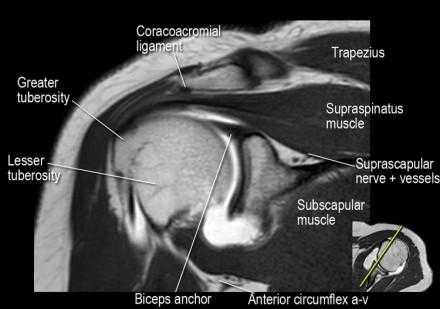

Нормальная корональная анатомия плечевого сустава и контрольный список

- обратите внимание на клюво-ключичную связку (coracoclavicular ligament) и короткую головку двуглавой мышцы (short head of the biceps).

- обратите внимание на клювоакромиальную связку (coracoacromial ligament).

- -

- обратите внимание на надлопаточный нерв и сосуды (suprascapular nerve and vessels)

- поищите импинджмент надостной мышцы за счет остеофитов в акромиально ключичном суставе или из-за утолщения клювовидноакромиальной связки.

- изучите верхний комплекс двуглавой мышцы и суставной губы, поищите подгубный карман илм SLAP-повреждение

- поищите скопление жидкости в подакромиальной сумке и повреждение сухожидия надостной мышцы

- поищите частичный разрыв сухожилия надостной мышцы в месте его прикрепления в виде кольцевидного повышения сигнала

- изучите область прикрепления нижней плече-лопаточной связки. Изучите нижний комплекс суставной губы и связок. Поищите HAGL-повреждение (humeral avulsion of the glenohumeral ligament).

- поищите повреждение сухожилия подостной мышцы

- обратите внимание на небольшое повреждение Хилл-Сакса

- изучите место прикрепления длинной головки двуглавой мышцы плеча к суставной губе (biceps anchor)